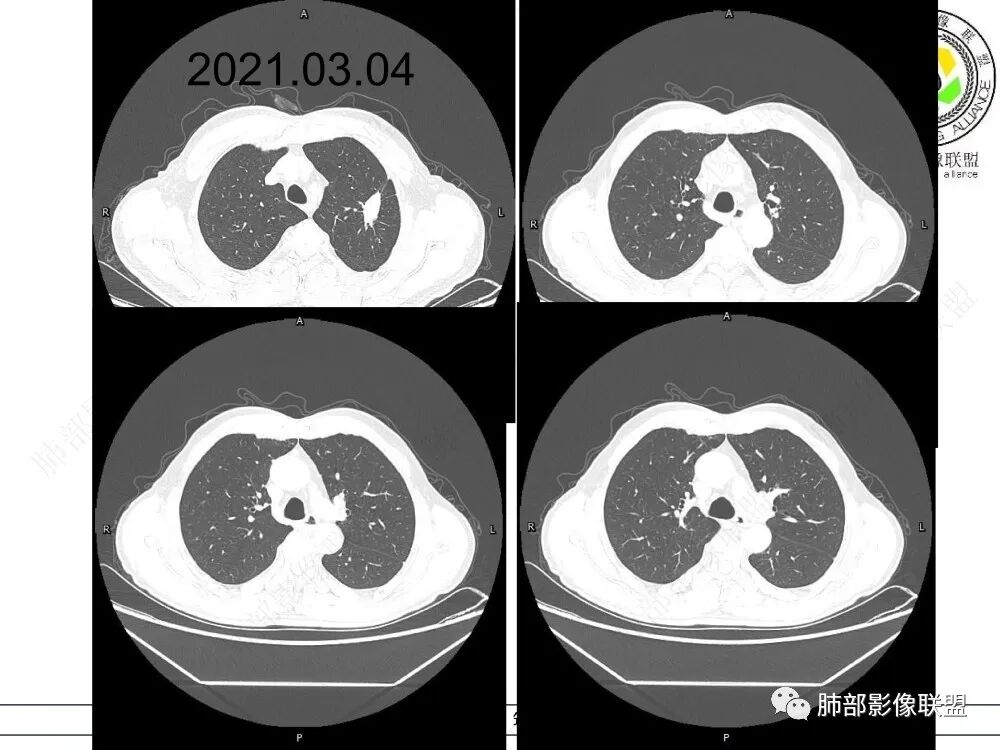

病史时间:2018年8月12日确诊左肺上叶肺腺ca射频消融,2020年1月13日左肺下叶未见结节,2021年3月14日新发双肺下叶(视频图)见4枚实性小结节,边清,目测低强化,胸膜下的结节(3个)与胸膜粘连的特点,无收缩力,前后1年余倍增明显结节,多发,支持炎性肉芽肿结节,隐球菌荚膜抗原检查,其次与转移鉴别,非随机,位置仅双肺下叶,可能性小,建议左肺下叶后基底结节定位穿刺活检!

1、临床特点:中老年男性,间断左侧胸痛2年余,复发1月余,既往左肺上叶占位穿刺确认肺腺癌,未行手术治疗,给予两次射频消融术,术后定期复查,1月前患者出现左下胸部阵发性刺痛,无畏寒、发热、咳嗽等其他临床症状,门诊胸部CT提示:左肺下叶新发结节。

2、影像特点:左肺上叶尖后段病灶结合病史考虑消融术后改变,双肺下叶胸膜下可见多发大小不等的实性结节,周围似乎有晕,边缘平直为主,未见深分叶,部分可见邻近胸膜牵拉,张力不高,增强后呈轻中度强化。